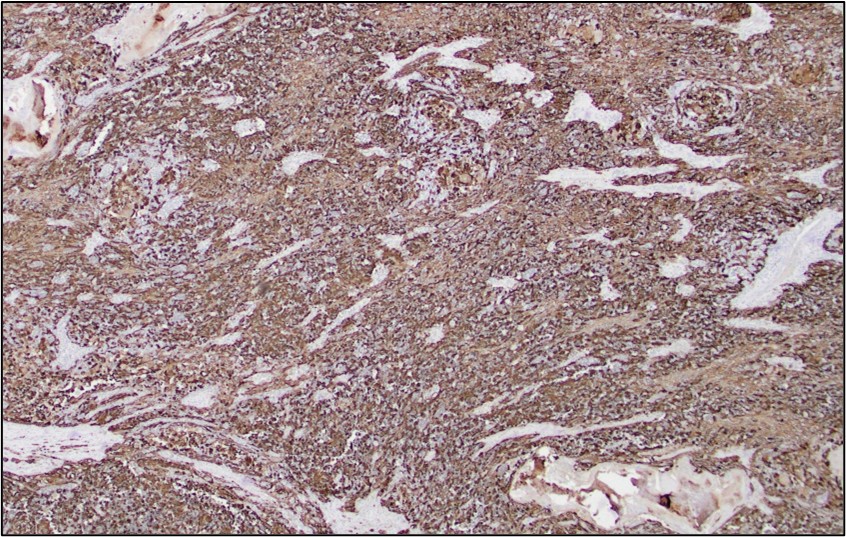

Much of the center of this mediastinal mass is effaced by extensive areas of necrosis and cystic degeneration. Sections were taken from the remaining thin peripheral rim of intact tissue that is surrounded by a variably thick, dense fibrous capsule. Neoplastic tissue is composed of highly cellular, infiltrates of plump spindloid to polygonal cells which are arranged in coalescing trabeculae and sheets and are intermingled with moderate to large numbers of small lymphocytes. These infiltrates multifocally infiltrate the surrounding capsule and are supported by small amounts of fine fibrovascular stroma which often forms dissecting thick bands and thinner septa. Frequently scattered within these infiltrates are small clusters of pale, polygonal, epithelial cells with glassy, keratinized, cytoplasm that are sometimes partially mineralized (Hassall’s corpuscles). The interstitium within the mass is also multifocally, mildly to moderately, expanded by pale poorly cellular fine fibrous stroma which often contains variably sized, deposits of basophilic, granular mineral. The majority of neoplastic polygonal to spindloid cells exhibit strong cytoplasmic staining with cytokeratin. Most of the small lymphocytes scattered within the mass were CD3 positive.The masses noted in the lung consist of similar, nodular mixed infiltrates of pale polygonal to spindloid cells intermingled with numerous small lymphocytes. These mixed infiltrates often dilated and fill pulmonary arteries and veins. Frequent scattered small deposits of mineral, foci of lytic and coagulative necrosis are also often scattered within these metastatic nodules.

Histologically, thymomas can vary greatly in appearance and in composition. Neoplastic cells are epithelial and originated from endoderm of the third pharyngeal pouch in the fetus2. Tumor cells may appear polygonal and/or spindloid, and are accompanied by variable, sometimes large, numbers of mature, non-neoplastic lymphocytes. As in this case, neoplastic cells exhibit cytoplasmic staining with cytokeratins and most of the small lymphocytes present within the tumor are small CD3+ T cells. Thymomas have been sub-categorized, based on cellular composition as lymphocyte predominant, epithelial predominate, or mixed. A variety of sub-types have also been identified (clear cell, spindle cell, pigmented)8. A clear association with prognosis and these sub-types has not been identified in veterinary medicine. In human medicine, the 2004 World Health Organization (WHO) classification scheme of thymic epithelial tumors was created to better correlate histologic findings with the clinical behavior of these tumors. This system is also based on the cell morphology of neoplastic epithelial cells and the relative proportion of non-neoplastic lymphocytes present and appears to be applicable to canine thymomas9.